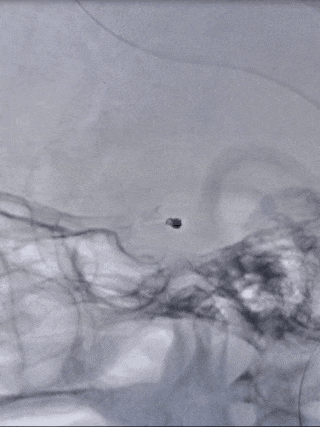

栓塞过程

Tethys®中间导引导管和Presgo®微导丝、微导管到位后,先行动脉瘤前下方瘤囊栓塞,陆续填入两枚Jasper®SS弹簧圈,最后行瘤颈填塞,以Jasper®SS弹簧圈收尾,完成瘤腔及瘤颈致密填塞。

术后即刻影像

本例病例为后交通动脉微小动脉瘤,使用Jasper®SS弹簧圈进行填塞和收尾,填塞过程较为稳定,圈体非常柔软,钻空能力强,分布较为均匀,收尾时可以有效覆盖瘤颈,达到致密填塞效果。